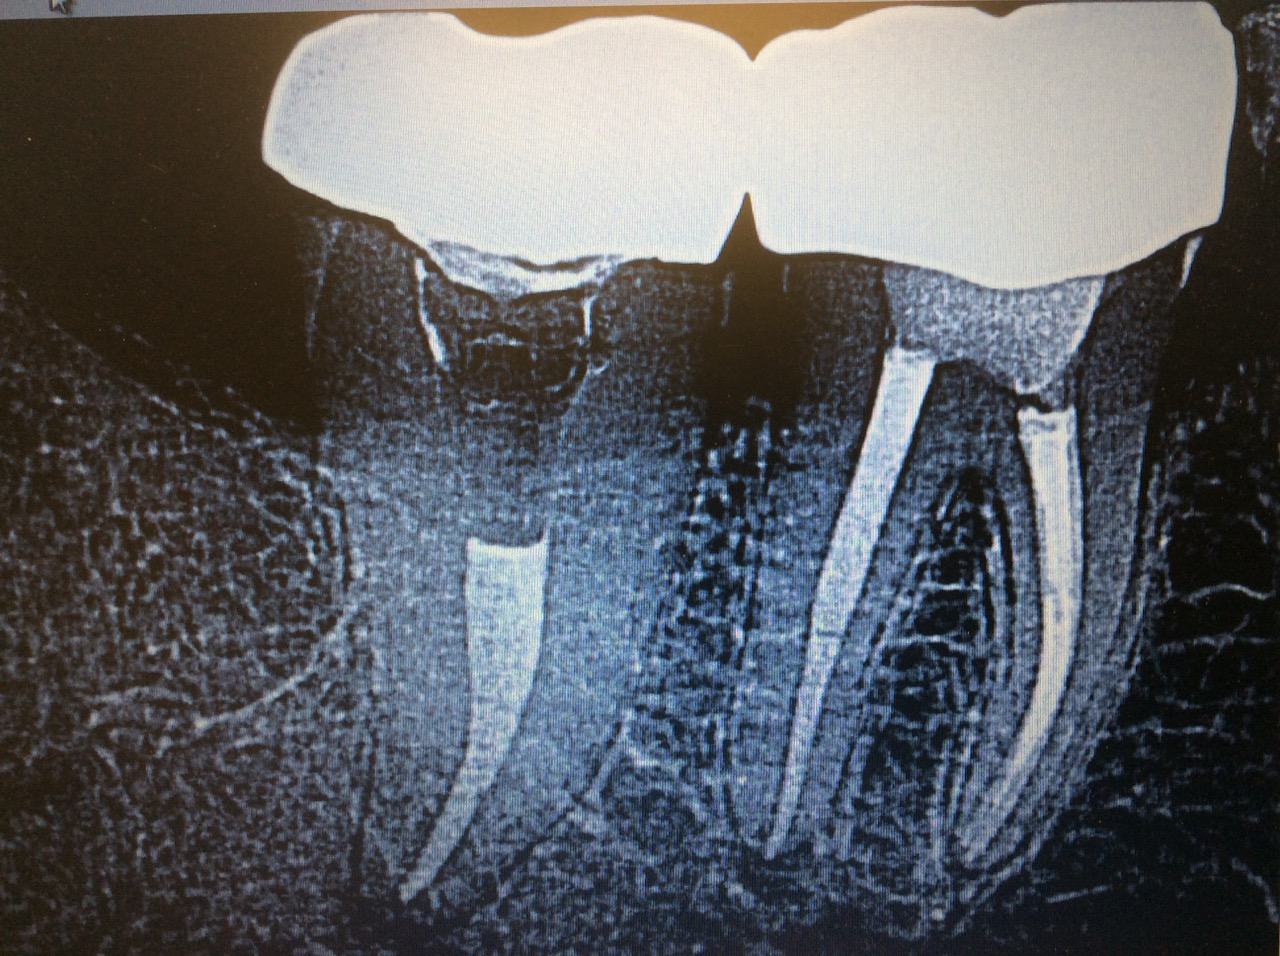

Through the complete exam and radiographs, I discovered that Don’s pain originated from tooth No. 31. The radiograph revealed an open mesial margin and periodontal ligament thickening at the apical portion of the root.

I also saw that Don had a crown done a few years ago, and he had gone back to his dentist several times for adjustments. As it turned out, the crown had an open mesial margin, which led to an undiagnosed abscess that lingered for six months (figure 1).

Don left my office with an antibiotic prescription and a referral to an excellent endodontist. He soon followed up with the endodontist and was successfully treated with a root canal and a new crown (figure 2).